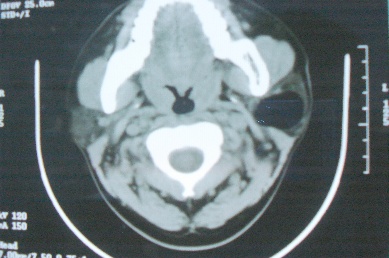

ct10755,男,28岁。发现左侧腮腺区肿块几年,今要求ct检查。左侧腮腺区低密度影,ct值-153hu。

左侧腮腺区囊状低密度影,ct值-153hu,考虑腮腺脂肪瘤。

病灶为一边界清晰脂性区,其内未见实质性组织.支持考虑:左侧腮腺脂肪瘤可能性大.

ct能定性的良性肿瘤不多,对脂肪瘤的诊断是比较有把握的,加大窗宽还可以看到里面有分隔

ct值-153hu,腮腺脂肪瘤。